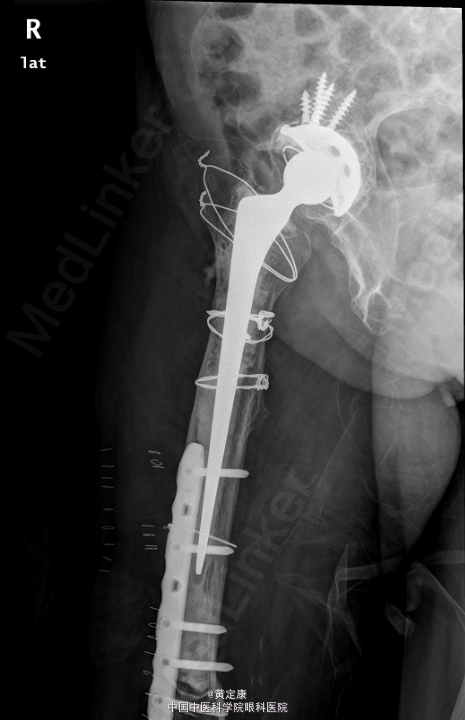

患者,女,82岁,因“摔伤致右下肢疼痛伴功能受限1天”入院。 患者1天前因外伤致右下肢剧烈疼痛,无法行走,。送至外院急诊,X线示“右股骨髁上骨折”,拟“右股骨髁上骨折”收治入院。

右膝部肿胀,膝关节活动受限,右足各趾活动感觉正常,末梢血运正常。石膏固定。检查提示:右股骨髁上骨折。

初步诊断: 右股骨髁上骨折 行[右]股骨骨折切开复位钢板内固定术